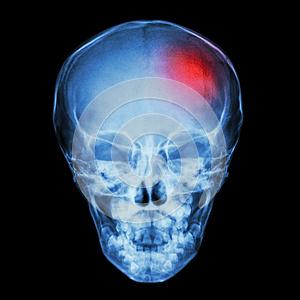

Для точного определения наличия или отсутствия повреждения кости врачи назначают рентгенографию. При этом интерпретацией результатов должен заниматься квалифицированный специалист, который способен заметить даже самые мелкие повреждения.

Главной задачей врача при интерпретации является точное выявление дефектов в структуре кости, так как существует риск перепутать сосудистую сетку с трещиной при анализе результатов краниографии.

Сложность также заключается в оценке степени тяжести перелома при переходе от лобной кости к затылочной области.

Линия разлома из-за особенностей строения кости имеет узкий и прямой вид, на рентгеновском снимке она определяется по нетипично темному оттенку, в то время как сосуды могут выглядеть серыми.

При серьезной травме врачи часто дополнительно назначают диагностику с помощью МРТ или КТ, так как эти методы позволяют провести более точную диагностику и предоставить детальное описание травмы.